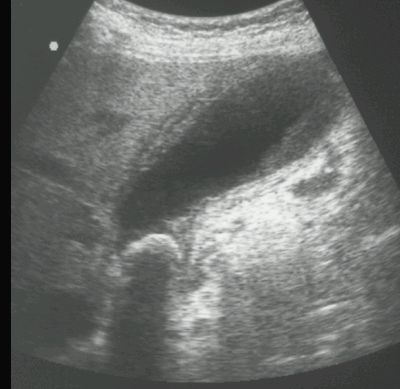

KAMICA PĘCHERZYKA ŻÓŁCIOWEGO Z ZAPALENIEM

USG